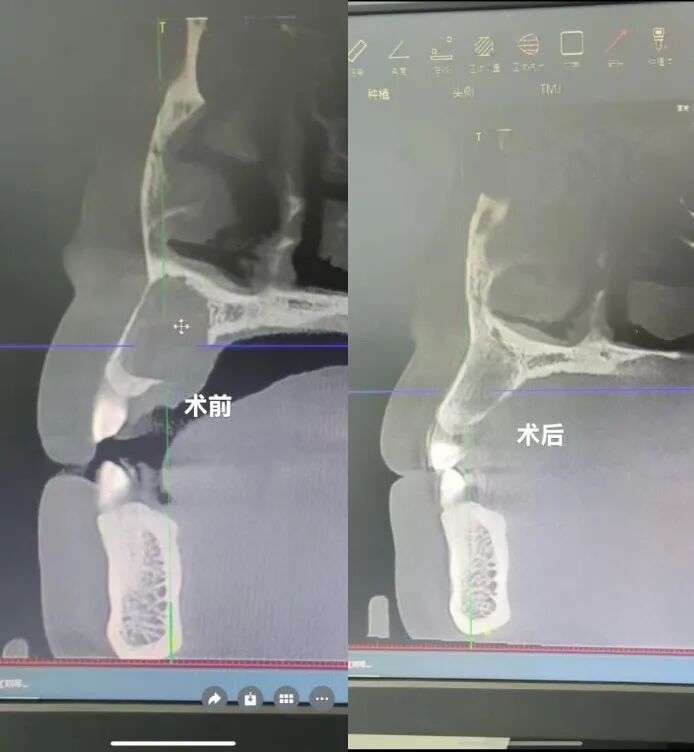

半年前,童女士因上前牙变色、颌骨前突并伴牙龈反复肿痛、流脓,辗转多家医院均被告知需手术治疗。出于对手术的恐惧及对面容影响的担忧,她迟迟未能接受治疗。得知我院周末特邀省级专家柳志文教授坐诊后,童女士前来求助。柳教授经系统检查并与科室刘琴文主任会诊后,充分尊重患者意愿,决定采用中西医结合的根管治疗方案,实现微创治愈。

治疗过程中,柳教授全程跟踪、精细调整,历时6个月,童女士症状逐步缓解,颌骨囊肿完全消退,面容自然恢复,终迎健康笑容。“没想到不用开刀也能治好,太感谢柳教授和市中医院了!”童女士感慨道。